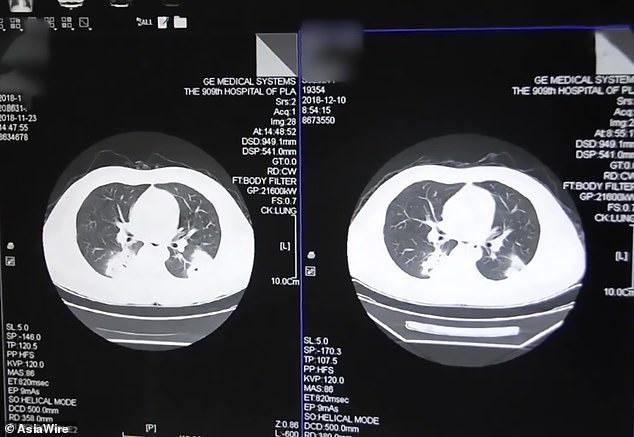

| Phổi của bệnh nhân bị nhiễm trùng do hít phải một loại nấm mốc. Ảnh: Dailymail. |

Sau đó, các bác sĩ phát hiện Peng bị nhiễm nấm nghiêm trọng trong phổi, gọi là bệnh nấm phổi. Nguyên nhân của nhiễm trùng là Peng hít phải bào tử nấm có trong tất bẩn.